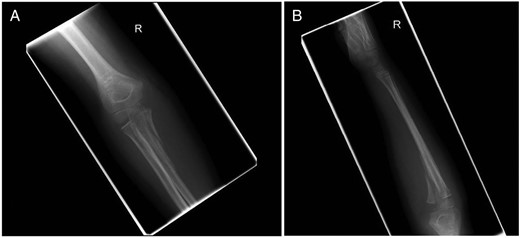

Five weeks following surgery, the fracture had clinically united and radiographs demonstrated maintenance of alignment and evidence of healing (Fig. 4). At a final review 4 months post-operatively he had a full range of motion of the elbow and forearm with no distal neurovascular deficit. The metalwork was not causing irritation and was therefore left in place.

(A) Anterior–posterior and (B) lateral radiographs of the right elbow. Images taken at 5 weeks post-reduction.